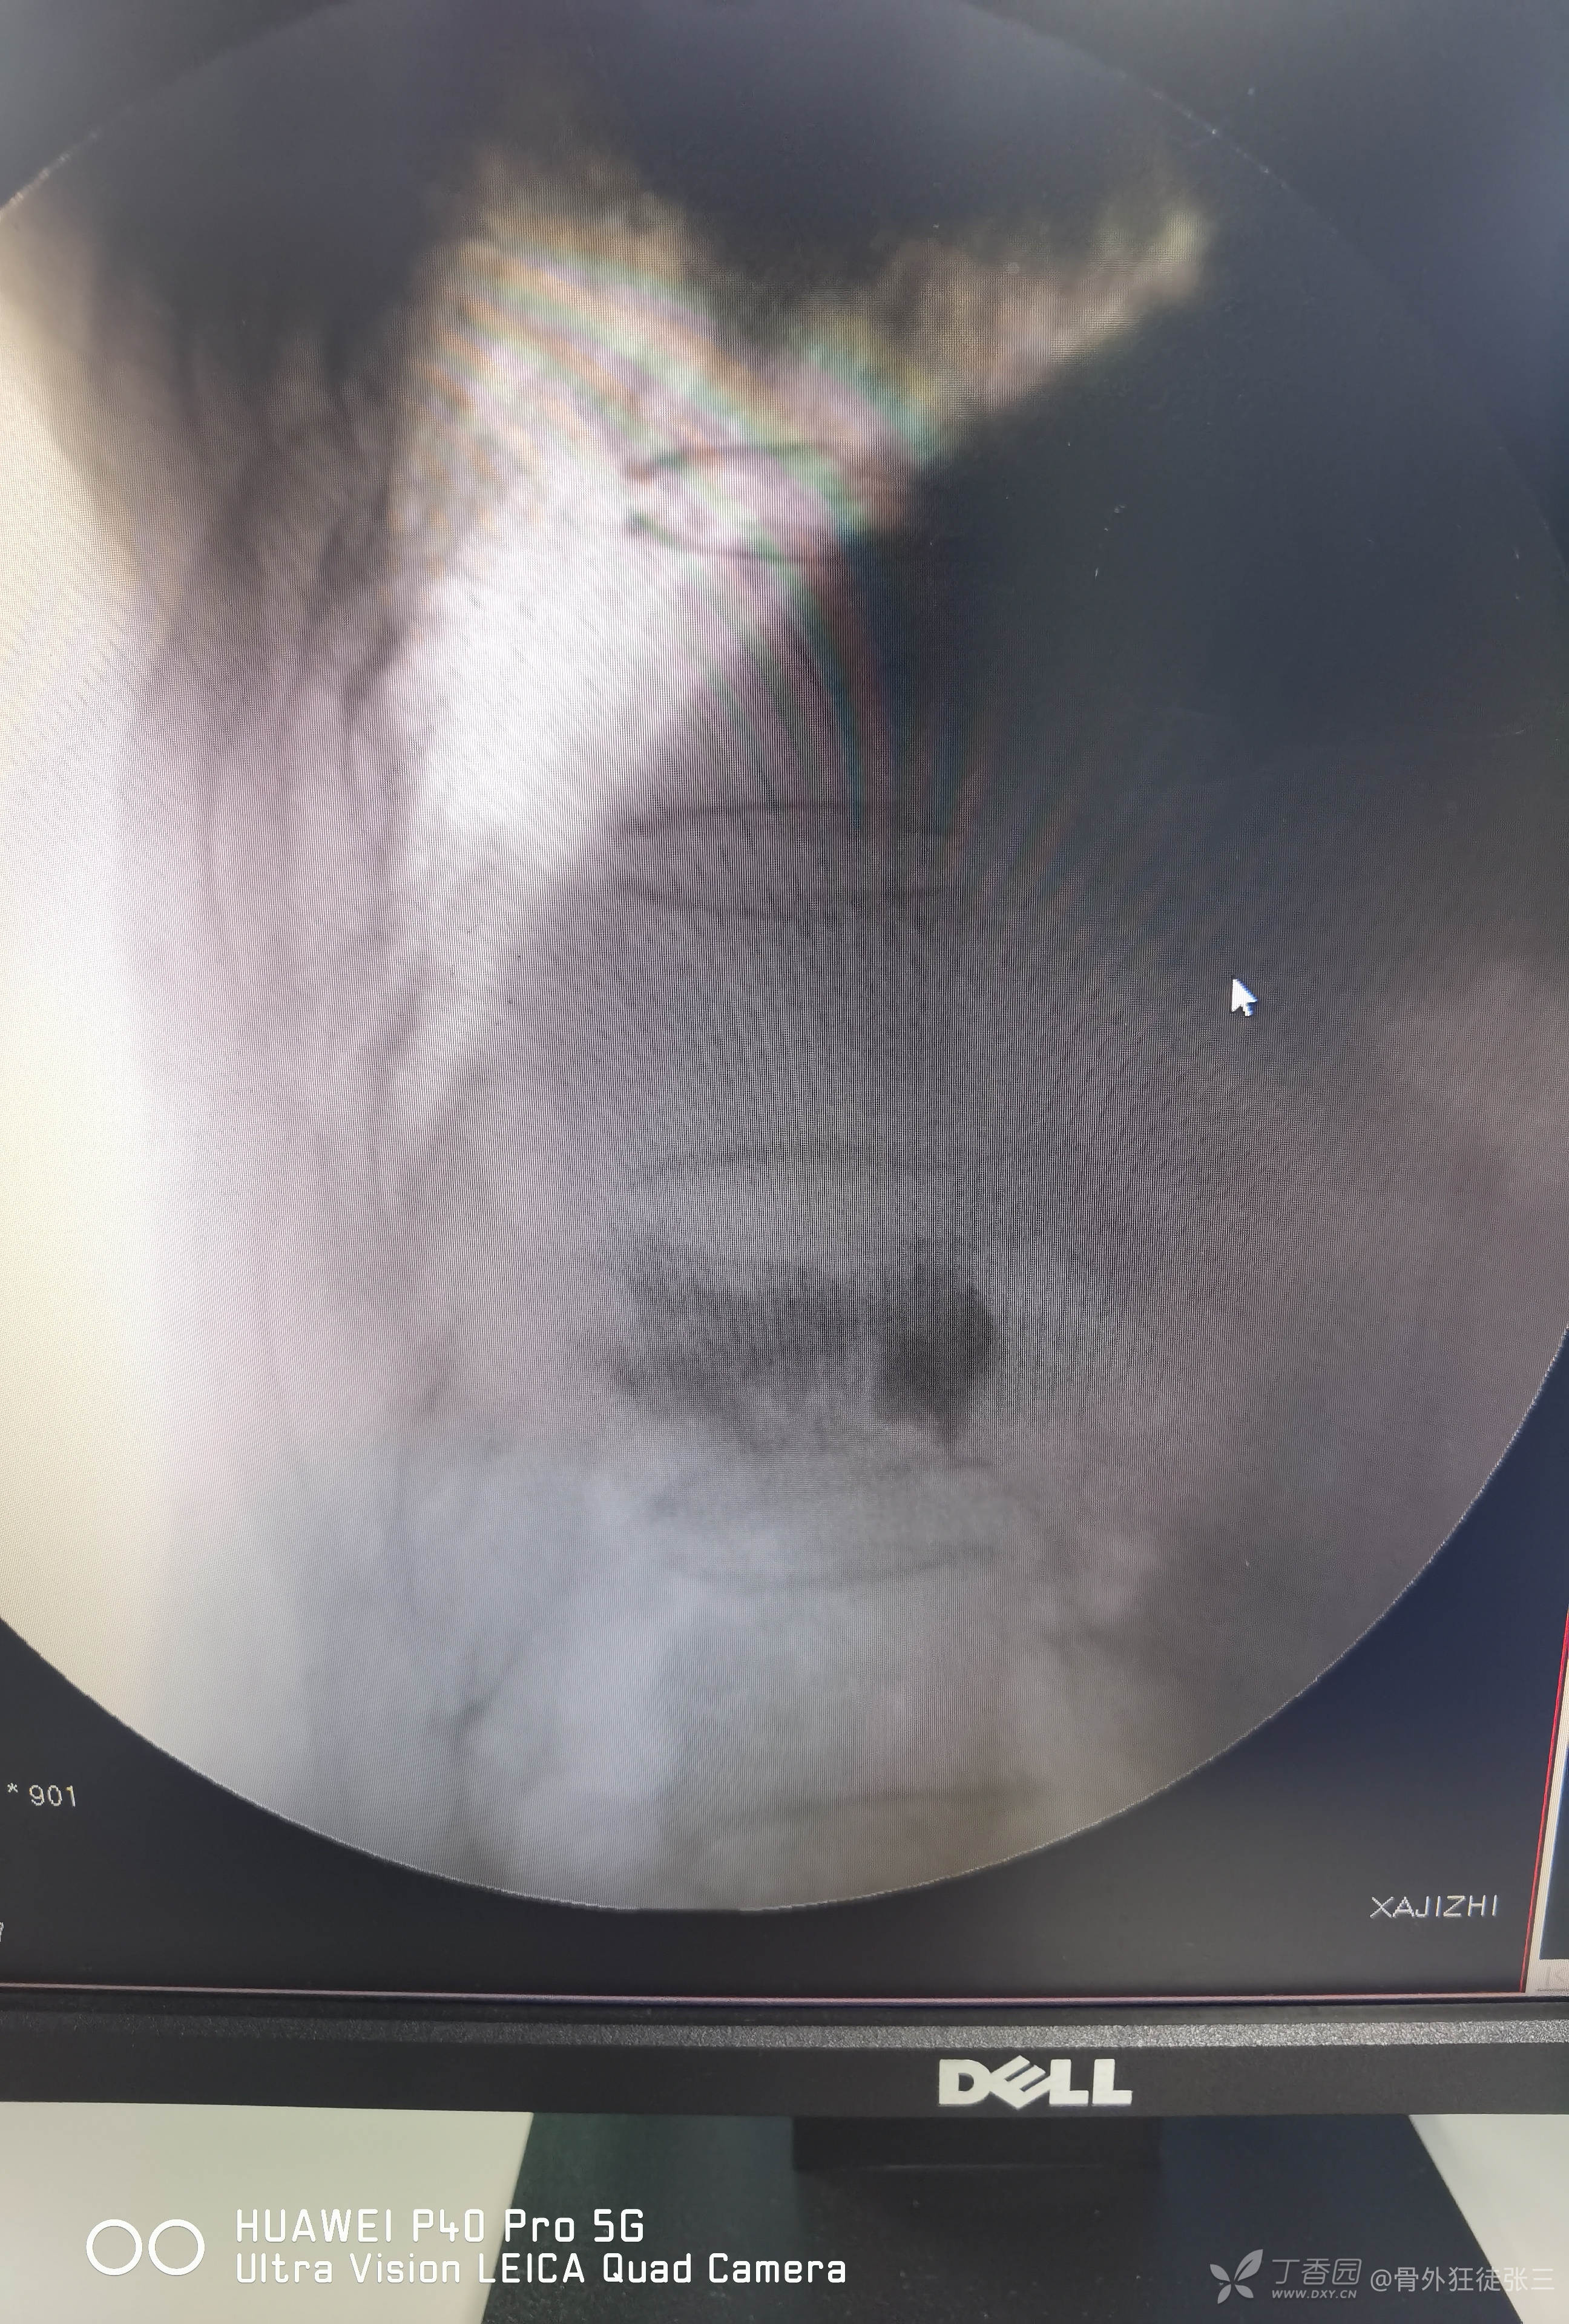

脆性骨折:胸12椎体压缩骨折椎体成形术1例

术前讨论后行经皮穿刺椎体成形术。

一共注入4ml骨水泥

复查X线显示,骨水泥弥散尚可,椎体高度恢复欠佳。

单侧穿刺,